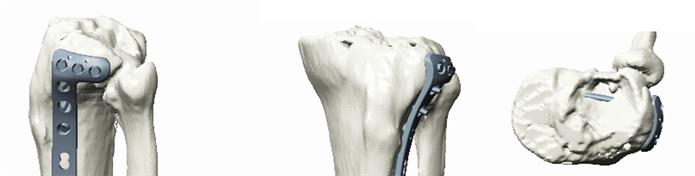

- 數(shù)字模擬內植物選擇及放置位置

聞泰數(shù)字骨科專業(yè)軟件平臺已預設聞泰百得全部內固定產品和器械,方便術前規(guī)劃和內植入物選擇

- 3D打印的骨折模型實物,供醫(yī)生進行手術模擬、內植物選擇、提前預彎,使板型更貼合患者

我們的解決方案提供多樣的3D打印技術,包括熱熔沉積技術(FDM),光固化技術(SLA)和激光燒結技術(SLS),可提供不同材質、不同尺寸、不同精度和不同打印速度的多種3D打印選擇。